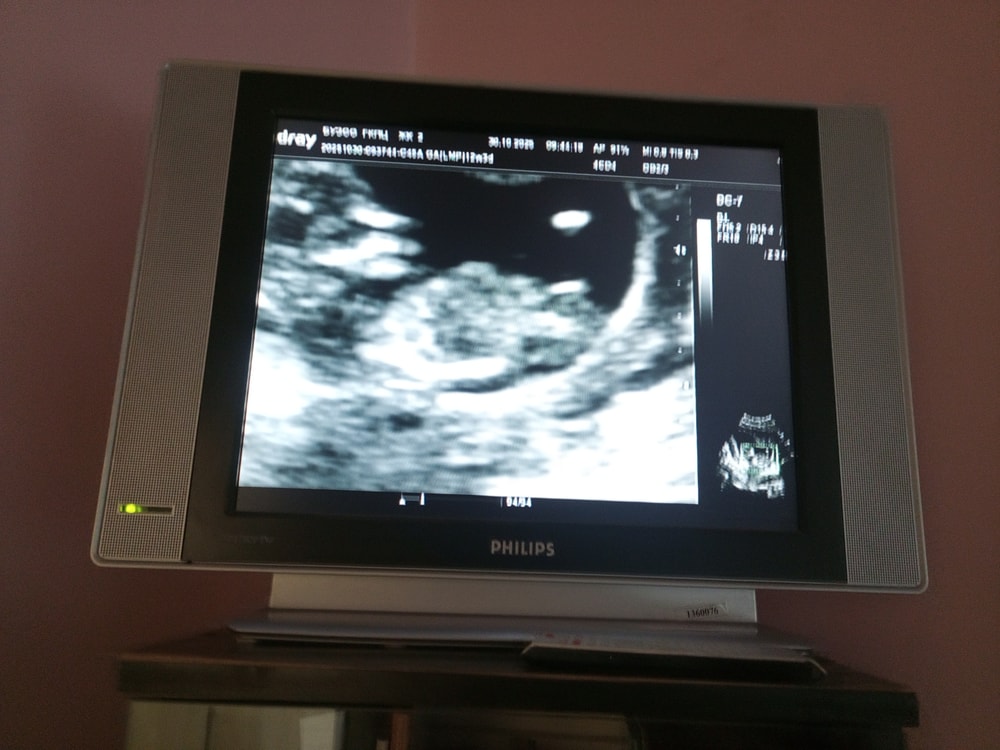

Невозможно установить пол в 12 недель беременности- на этом сроке половые органы еще не имеют сколь-нибудь отчетливой половой дифференциации.

Уж не знаю, где вы там что видите... Мне в 12 недель сказали что "больше похоже на девочку" в итоге на втором скрининге Четко было видно что мальчик)

У нас так же выглядело , в итоге мальчик 😅

Девочка😍 Кстати, снимок очень похож на мой со второй доченькой

Я просто смотрю половой бугорок, у меня с обоими совпадало)

Девочка